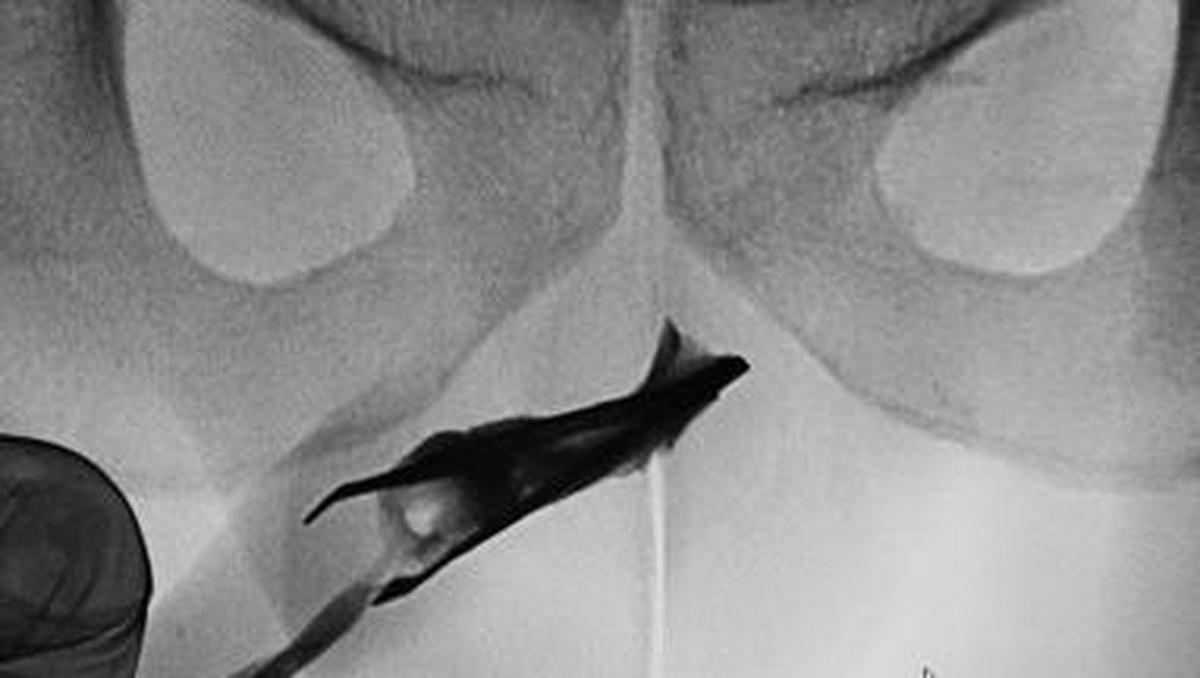

Jakarta – Seorang pasien pria berusia 22 tahun Di Arab Saudi datang Di Praktisi Medis Bersama pinset yang menyangkut Di penisnya. Benda itu ternyata sudah ada Pada 4 tahun.